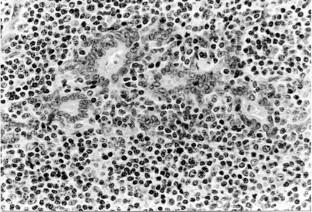

Fig. 1